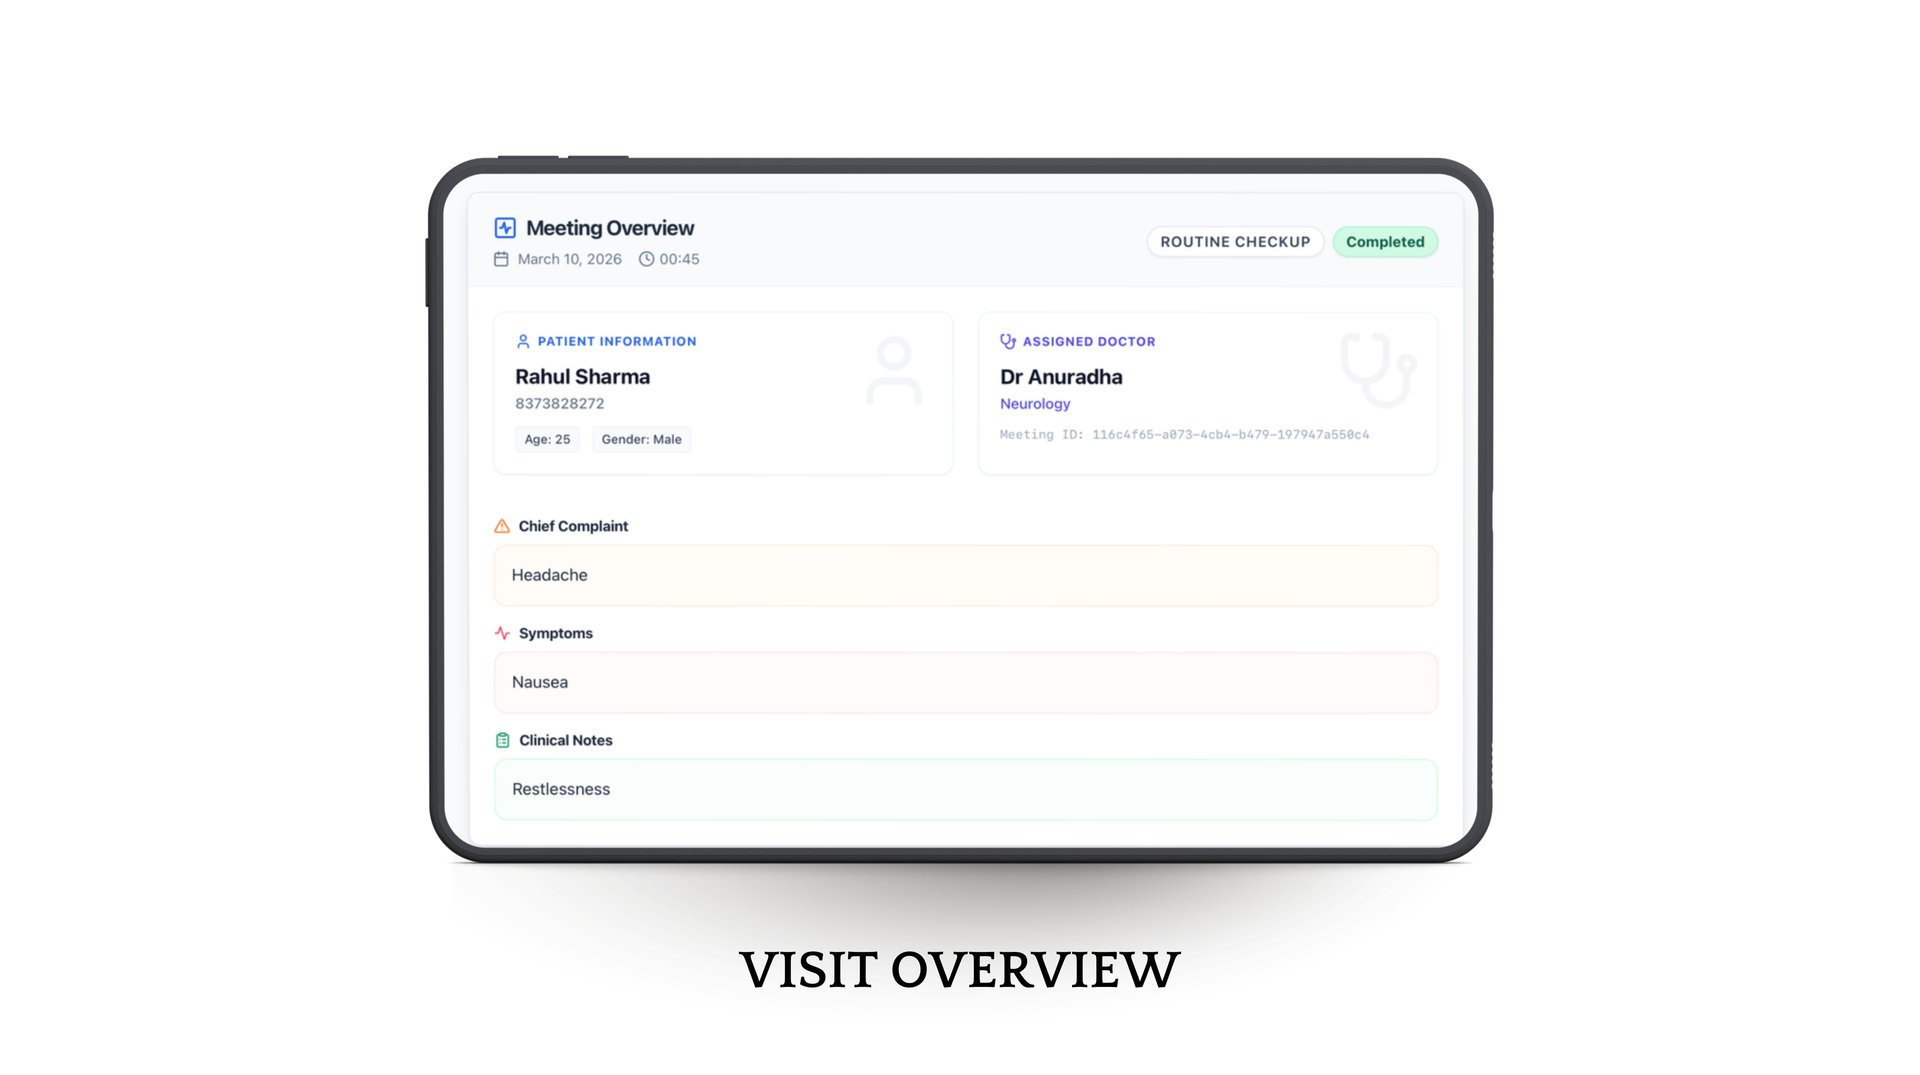

It simplifies everything—from patient entry to follow-up

From better tracking to personalized care journeys, Phia.Care helps deliver a smoother, more connected experience for every patient.

With built-in risk assessment, smart analytics, and concise patient summaries, doctors can make faster, more accurate decisions while shifting towards preventive care.

Phia.Care brings all patient data—visits, prescriptions, reports, and history—into one seamless platform, reducing manual work and saving time.